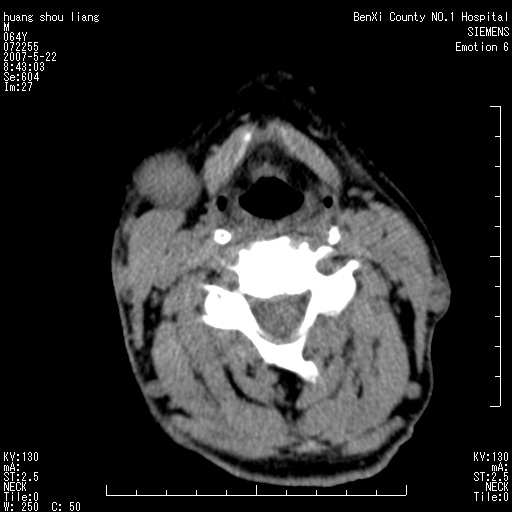

男性,64岁。颈部包块8年。最近增大。

对不起大家,可能是片子发太多有点乱,正常腮腺在下颌角的外侧,颌下腺在下颌体的中部内侧,本例在下颌角内侧偏下,和腺体一点关系都没有,从vrt和mpr上可以很明显看出来,再者肿块是好多粘连在一块的,大家在仔细看看,左侧可能也是吧,我还是考虑为肿大的淋巴结融合在一块,但性质??????

右侧腮腺下部均匀软组织密度肿块,外形不规则,与周围组织分界清晰,考虑右侧腮腺混合瘤或多形性腺瘤。

大家好,病理结果出来了,如大家所说,颌下腺混合瘤。

唉,解剖没学好吧,我诊断错了,不过还是有些不理解回去我在多看看书,谢谢大家的参与,以后我还会奉献好的病例。